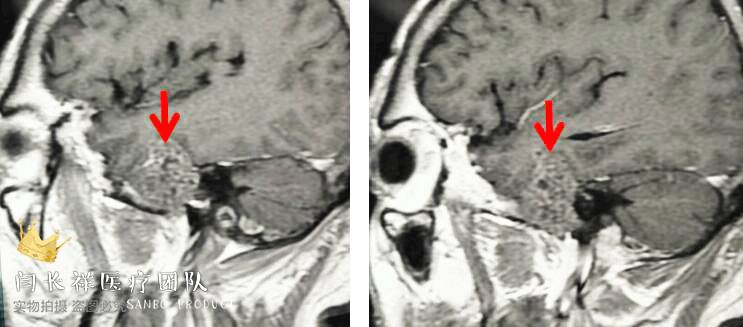

术前MRI矢状位T1增强。

术前MRI冠位T1增强示病灶主体位于硬膜外,侵蚀中颅窝底骨质并朝颞下窝、翼腭窝生长。